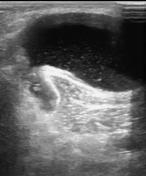

Một số hình ảnh

Hình ảnh siêu âm, MRI